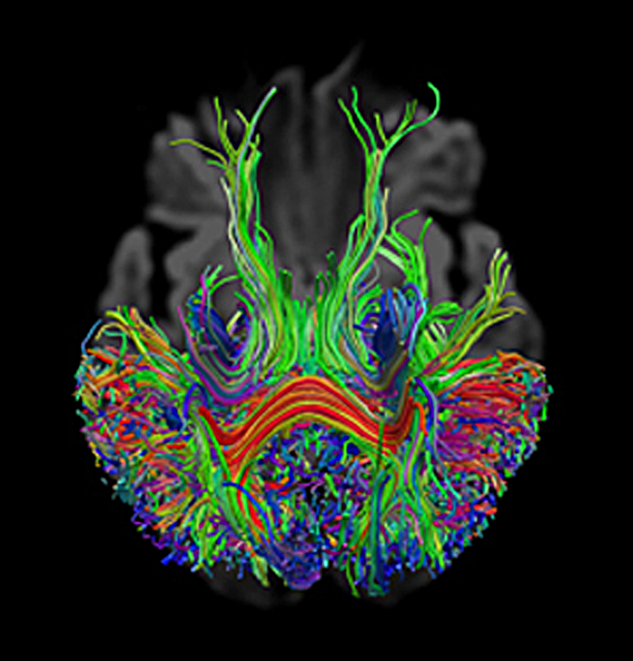

Diffusion Tensor Imaging is also called DTI or tractography. It is a mathe­ma­ti­cal pro­cess­ing tech­ni­que of diffusion-weighted measurements and potentially valuable for brain diagnostics in areas of anisotropic diffusion, al­lo­wing the depiction of the di­rec­tion and, possibly, interruption of tissue tracts. It is mainly applied to white mat­ter axonal fiber bundles and, at the time being, re­mains a research technique [⇒ Hag­mann 2006, ⇒ Nucifora 2007].

DTI relies on algorithms that assemble two- or three-dimensional visualizations of main white matter axonal fiber bundles. It allows to delineate fiber bundles from each other, as well as from gray matter and CSF (Figure 11-12).

Figura 11-12:

Tractography calculated from DW imaging data. The signal of the neural tract is stron­gest when the dif­fu­­sion gra­dient is di­rec­ted orthogonally to white matter bund­les, such as in the corpus callosum.

The different diffusion directions (gradient direc­tions) x, y, and z are color-coded in these images: x = red, y = blue, and z = green.

For MR tractography fiber bundles must be aligned in one direction only and must not intersect. The tracts (fiber bundles) depicted on such an image are not the fi­bers per se, but local dif­fu­sion maxima.